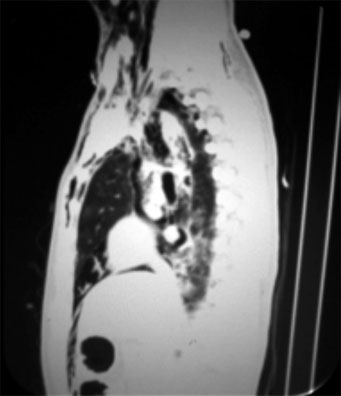

La tomografía computada de cuello y tórax mostró evidencia de neumotórax residual derecho de menos del 10% y neumotórax izquierdo resuelto. También hubo la presencia de un pequeño hematoma al nivel del tronco supraaórtico del lado izquierdo con neumomediastino (superior) (figuras 4 y 5).